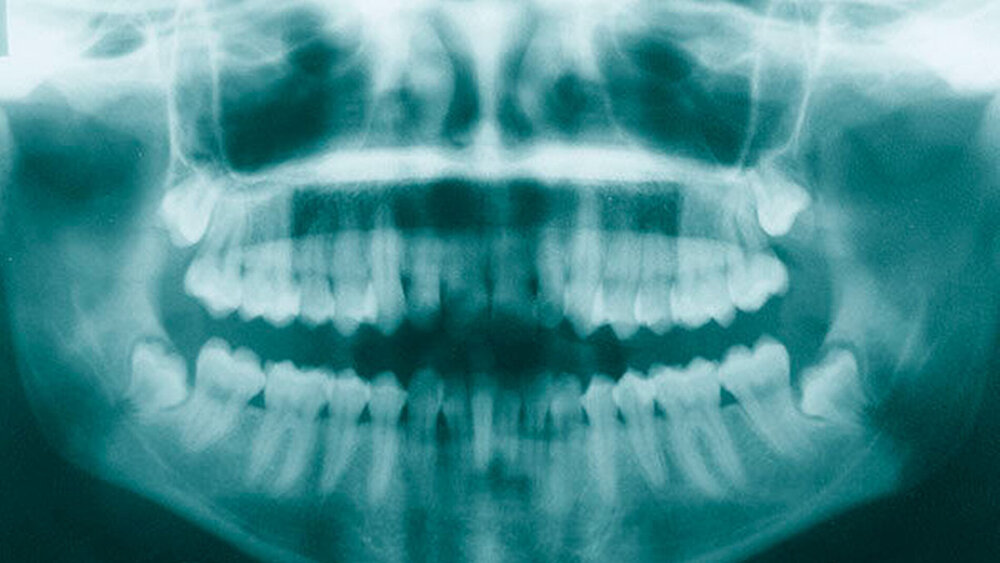

Eine gesunde 23-jährige Patientin stellte sich mit einem submukösen Abszess und beginnendem Wangeninfiltrat rechts bei Zustand nach Weisheitszahnentfernung der Zähne 18, 28, 38, 48 (Abbildung 1) alio loco im Notdienst unserer MKG-chirurgischen Abteilung Anfang 2015 vor. Nach Abszessinzision, Drainage und Gabe eines oralen Antibiotikums (Clindamycin) kam es zunächst schnell zu einer Verbesserung der klinischen Situation, so dass nach unserer Behandlung die weitere Nachsorge durch den niedergelassenen Zahnarzt erfolgte.